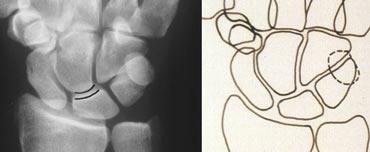

Phim X-quang cổ tay tư thế thẳng (PA) và hình minh họa sơ đồ cho thấy sự gián đoạn của cung cổ tay thứ nhất

Gián đoạn các cung cổ tay

Một cung được coi là gián đoạn khi không thể vẽ theo một đường cong trơn liên tục. Sự gián đoạn của một trong các cung cho thấy có gãy xương hoặc đứt dây chằng dẫn đến bán trật khớp hoặc trật khớp.

Ở hình bên trái, có thể nhận thấy sự gián đoạn của cung I tại khớp nguyệt-tháp.

Hình bên trái cho thấy sự gián đoạn của cung cổ tay thứ hai tại khớp thuyền-nguyệt và khớp nguyệt-tháp. Mặc dù có một khoảng hở ở cung thứ nhất, nhưng vẫn có thể vẽ theo một đường cong trơn liên tục, do đó cung I được coi là còn nguyên vẹn.

Sự gián đoạn của cung cổ tay thứ ba được minh họa trong trường hợp tiếp theo ở hình bên trái. Có hiện tượng bậc thang bất thường tại khớp đầu-móc.